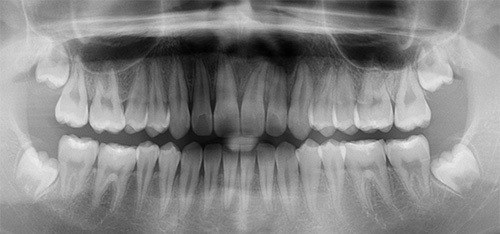

Orthodontic Treatment X-ray - Before

After Series of Teeth Extractions, Upper Left Canine Unerupted.

Ready to Start Ortho Treatment